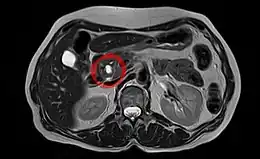

La tumeur intracanalaire papillaire et mucineuse du pancréas (TIPMP) est une variété de tumeur kystique du pancréas exocrine caractérisée par une dilatation du canal pancréatique principal ou des canaux secondaires.

La TIPMP se développe à partir de l’épithélium du système canalaire pancréatique et sécrète un mucus épais[1],[2],[3]. Cette sécrétion de mucus est à l’origine d’une dilatation canalaire « kystique » intéressant soit le canal pancréatique principal soit les canaux secondaires[3],[2],[1].

Échographie

L'échographie explore difficilement le pancréas compte tenu de sa position profonde dans l'abdomen. Elle peut toutefois mettre en évidence une dilatation canalaire (> 6 mm) dans le cas d'une TIPMP du canal pancréatique principal[3]. Le contenu canalaire est parfois non strictement anéchogène[3]. Une TIPMP des canaux secondaires se manifeste par une lésion kystique volontiers lobulée[3].